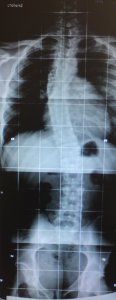

Dateianhänge

DSC00450___Kopie_1.jpg

DSC00450___Kopie_1.jpg (8.49 KiB) 10770 mal betrachtet